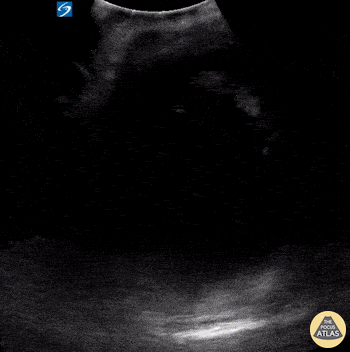

A middle-aged female with a history of colon cancer presented to the ED with constipation and abdominal pain. A recent colonoscopy had revealed rectosigmoid adenocarcinoma. Her physical exam was notable for a distended abdomen that was tender to palpation. POCUS revealed the presence of a large, complex, cystic structure within the pelvis. Subsequent CT confirmed a loculated fluid collection within the pelvis compressing the rectum and sigmoid colon; this mechanical obstruction was likely contributing to patient’s constipation. Differential diagnosis included loculated ascites versus cystic tumor. Kyla Walworth, MS-4 & Matthew McDowell, PGY-1 Central Michigan University College of Medicine